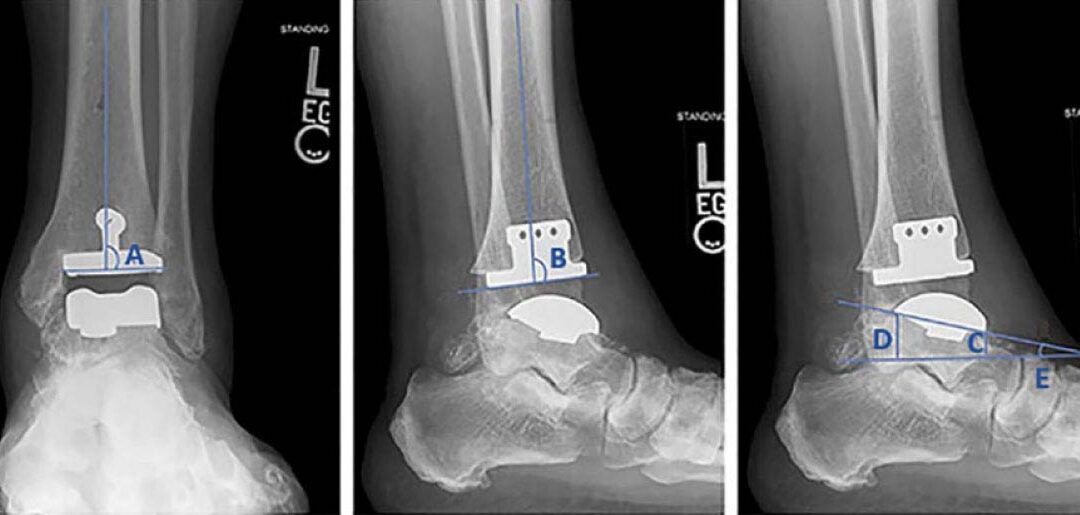

In this longer-term follow-up of a limited cohort (48 patients/50 ankles, average age at index surgery: 64 years), Salto Talaris fixed-bearing total ankle arthroplasty demonstrated good long-term survival (Kaplan-Meier estimated survivorship was 84.2%) with relatively low rates of revision or other complications. Patient-reported outcome and range of motion measures revealed good stability.

Source: Veale M, Endo A, Veale N, et al. Salto Talaris fixed-bearing total ankle arthroplasty: long-term results at a mean of 10.7 years. Foot Ankle Orthop. 2024;9(1):24730114231225458. doi: 10.1177/24730114231225458.